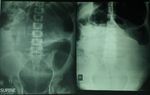

Int J Pediatr, Vol.8, N.1, Serial No.73, Jan. 2020                                        10744Ghahremani et al. and fluid content were observed with pelvic X-ray showed a dilated bowel with decreased peristalsis. Abdominal and a bent inner tube view (Figure.1). Fig.1: Abdominal X-ray image (lying / standing) showing fluid-air surface of dilated colon with inverted -U view. Due to the patient's severe pain and X-ray around its mesentery near the pregnant findings that suspected intestinal uterus was seen; then torsion was opened obstruction, a laparotomy was performed and there was no evidence of sigmoid with a median incision and a highly dilated gangrene (Figure.2). sigmoid colon rotated about two times Fig.2: Picture taken during explorative laparotomy, showing dilated sigmoid volvulus on the right side and pregnant uterus on the left side. Int J Pediatr, Vol.8, N.1, Serial No.73, Jan. 2020 10745